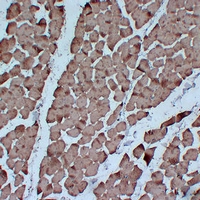

Immunohistochemical analysis of Actin pan staining in human skeletal muscle formalin fixed paraffin embedded tissue section. The section was pre-treated using heat mediated antigen retrieval with sodium citrate buffer (pH 6.0). The section was then incubated with the antibody at room temperature and detected using an HRP conjugated compact polymer system. DAB was used as the chromogen. The section was then counterstained with haematoxylin and mounted with DPX.